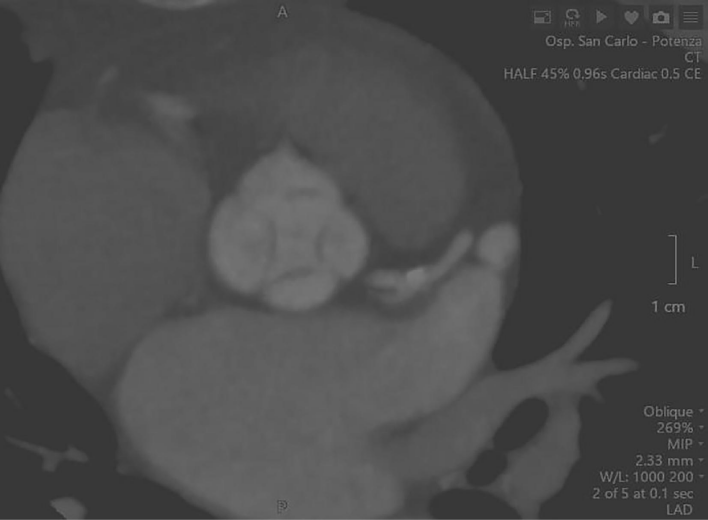

一名 54 岁的女性患者于 2024 年 2 月首次到他们诊所就诊,主诉为劳力性呼吸困难。患者无合并症,否认药物使用和吸烟史。心电图显示患者左心室肥厚。经胸超声心动图示:1)左心室增大,心室壁厚度正常(舒张末期直径 54 mm,室间隔 10 mm,后壁 10 mm,舒张末期容积指数 66 mL/m2); 2)收缩功能保留,舒张功能受损,射血分数 65%,主动脉瓣中心性反流导致重度主动脉关闭不全,主动脉根部和升主动脉尺寸正常,没有其他瓣膜异常。术前经食管超声心动图 (TEE)显示主动脉瓣四叶式畸形,根据 Hurwitz 和 Roberts分型被归类为 A 型,其特征是四个完全相等的瓣叶。计算机断层扫描 (CT) 证实了四叶式主动脉瓣并排除了冠状动脉疾病。